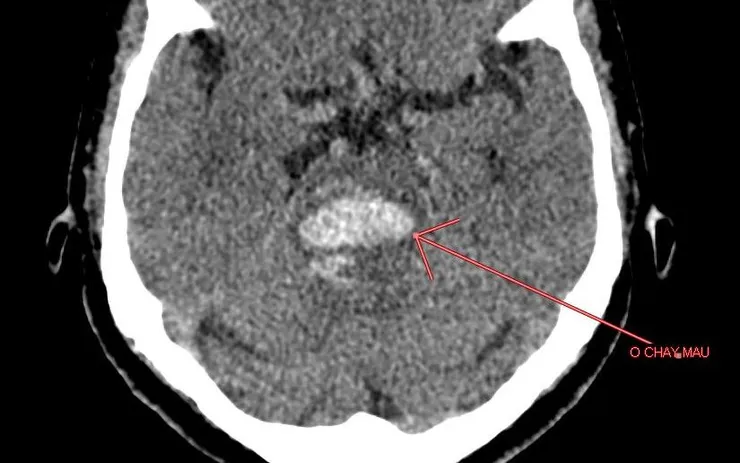

Trường hợp người bệnh Đ.T.X., 63 tuổi, nhập viện với huyết áp 170/90 mmHg, được chỉ định chụp CT và phát hiện ổ chảy máu trong não. Một trường hợp khác, bệnh nhân V.Đ.T., 69 tuổi, vào viện với huyết áp 210/100 mmHg, cũng cho thấy hình ảnh chảy máu não trên phim chụp. Các bác sĩ cho biết đây đều là những ca điển hình của biến chứng nguy hiểm khi tăng huyết áp không được kiểm soát.

Theo các bác sĩ, chảy máu não là một trong những biến chứng nặng nề nhất của tăng huyết áp, thường xảy ra đột ngột và có thể gây liệt, hôn mê hoặc tử vong. Nguy cơ tăng cao ở những người bỏ thuốc điều trị, ăn mặn, thường xuyên căng thẳng hoặc thay đổi thời tiết đột ngột.